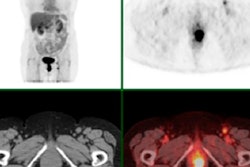

The partnership will allow users of ScImage's Picom365 enterprise PACS software to access Invia's 4DM for nuclear cardiology advanced quantification onsite, via the cloud, or using a combination of the two, the company said.